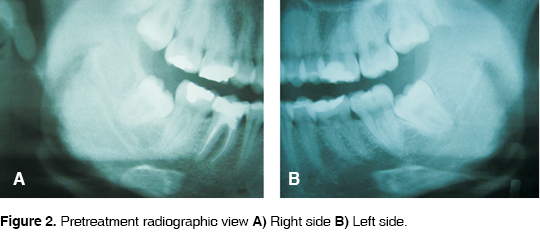

A 21 year old woman was admitted in the Clinica de Cirugía Maxilofacial de la Facultad de Estomatología, Universidad Autónoma de San Luis Potosí (Maxillofacial Surgery Clinic of the Stomatology School of the University of San Luis Potosi) for extraction of lower third molars. The patient informed of moderate pain. Clinically slight erithema of the mucosa in the right and left third molar area is observed (Figures 1A and 1B). Radiographically, both third molars were classified as class I, mesioangled with convergent roots with respect to the second molar, according to classification of Sanchez Torres19 (Figures 2A and 2B). It is decided to surgically remove both third molars under infiltration local anesthesia.